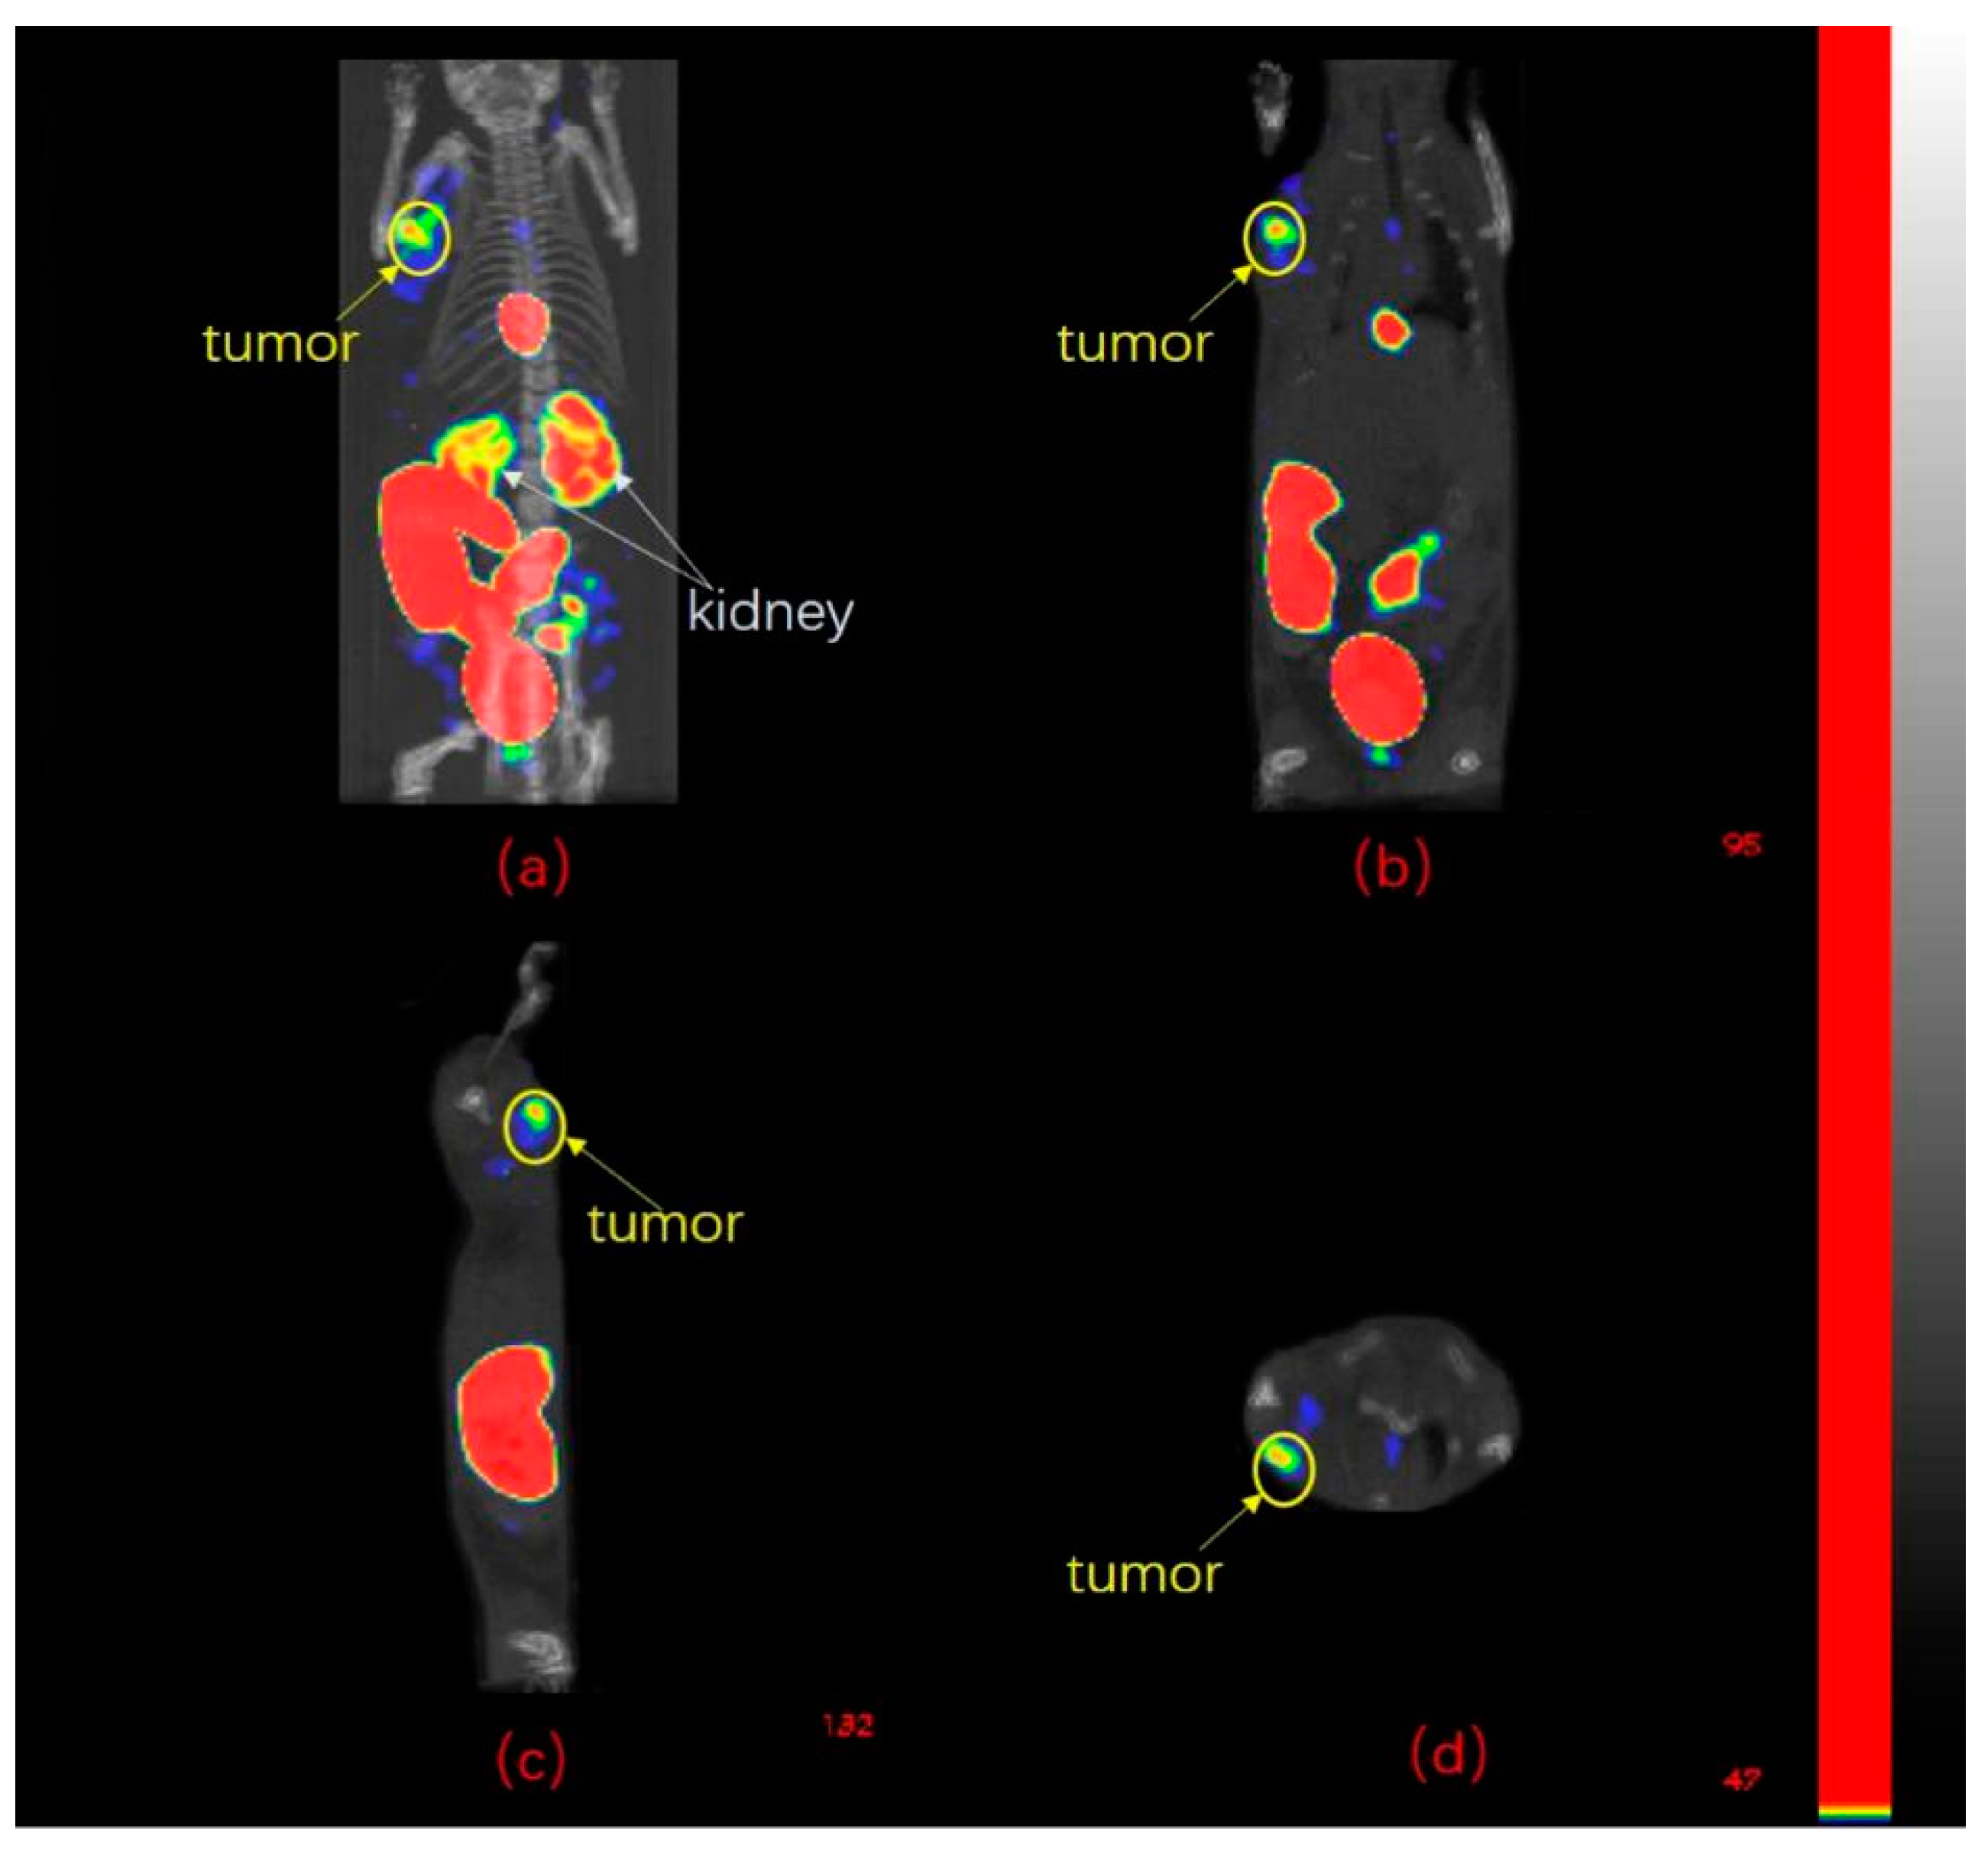

2.6. SPECT/CT Imaging Studies

4.8. SPECT/CT Imaging Studies